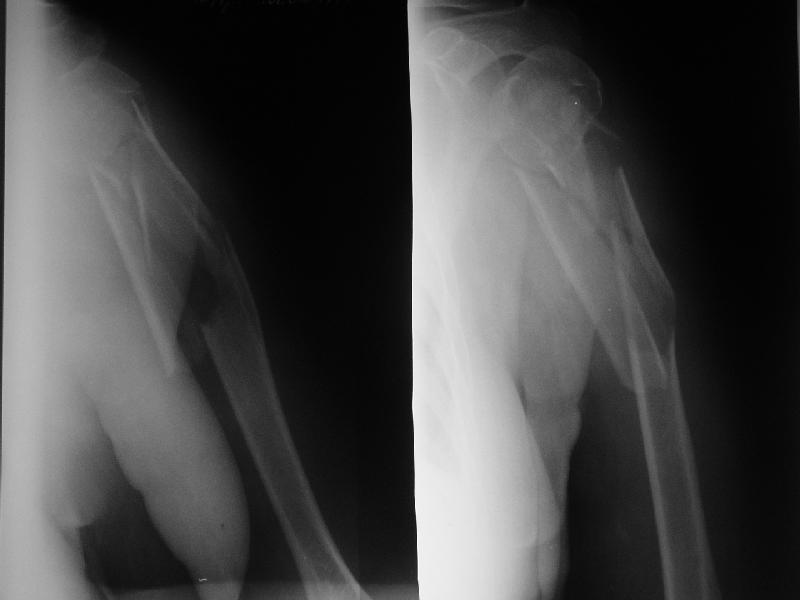

Re: Оскольчатый перелом плеча

Djoldas Kuldjanov 17 Август 2006, 14:00

Доминирующая ли рука и какая профессия?

Если выбор на интрамедулярный штифт, я бы сделал КТ головки, информация необходима для определения вовлечения головки в перелом, имеется опасность

расколочения и для ориентира расположения блокирующих шурупов.

Другой вариант, небольшой гипс на локтевой сустав как груз для тракции, повязкой за кисть выше-вниз можно контролировать сгибание и разгибание на место перелома, небольшая отводящая подушка в живот (у женщин молочная железа в зоне перелома

создает варус)сделать ренген снимки через одну недели. Перелом низкоэнергетический, может быть, без операции обойдется.

"Рука не доминирующая, но тоже нужна" - А.Н. Челноков. Больная уже лечилась консервативно в гипсовой повязке и на вытяжении, в настоящее время настаивает на оперативном лечении.

Есть и другие косые снимки, на которых не определяется вовлечение головки, если успеем - сделаем КТ. Спасибо за интерес к нашему случаю.

Ув. коллеги. Интересно, насколько разрушена головка, особенно ее артикулирующая поверхность, может для начала сделать КТ головки.

На счет операции - стоит ли ее вообще делать, куда Вы собираетесь забить стержень, на расколете ли головку, если она еще целая. В любом случае Вы

не добъетесь стабильной фиксации, прийдеться иммобилизировать где-то на месяц. Вопрос: какова будет функция после травматичной операции, а она

имеенно таковой будет и последующей иммобилизации. ВЧКДО сделать не получиться - не за что зацепиться.

> Ув. коллеги. Интересно, насколько разрушена головка, особенно ее

> артикулирующая поверхность, может для начала сделать КТ головки.

По нескольким снимкам в чуть разых проекциях она не фрагментирована. А если и были трещины, за прошедшие 3 недели они "слиплись", очевидно. А КТ если сделаем - еще можем испугаться увиденного :-)